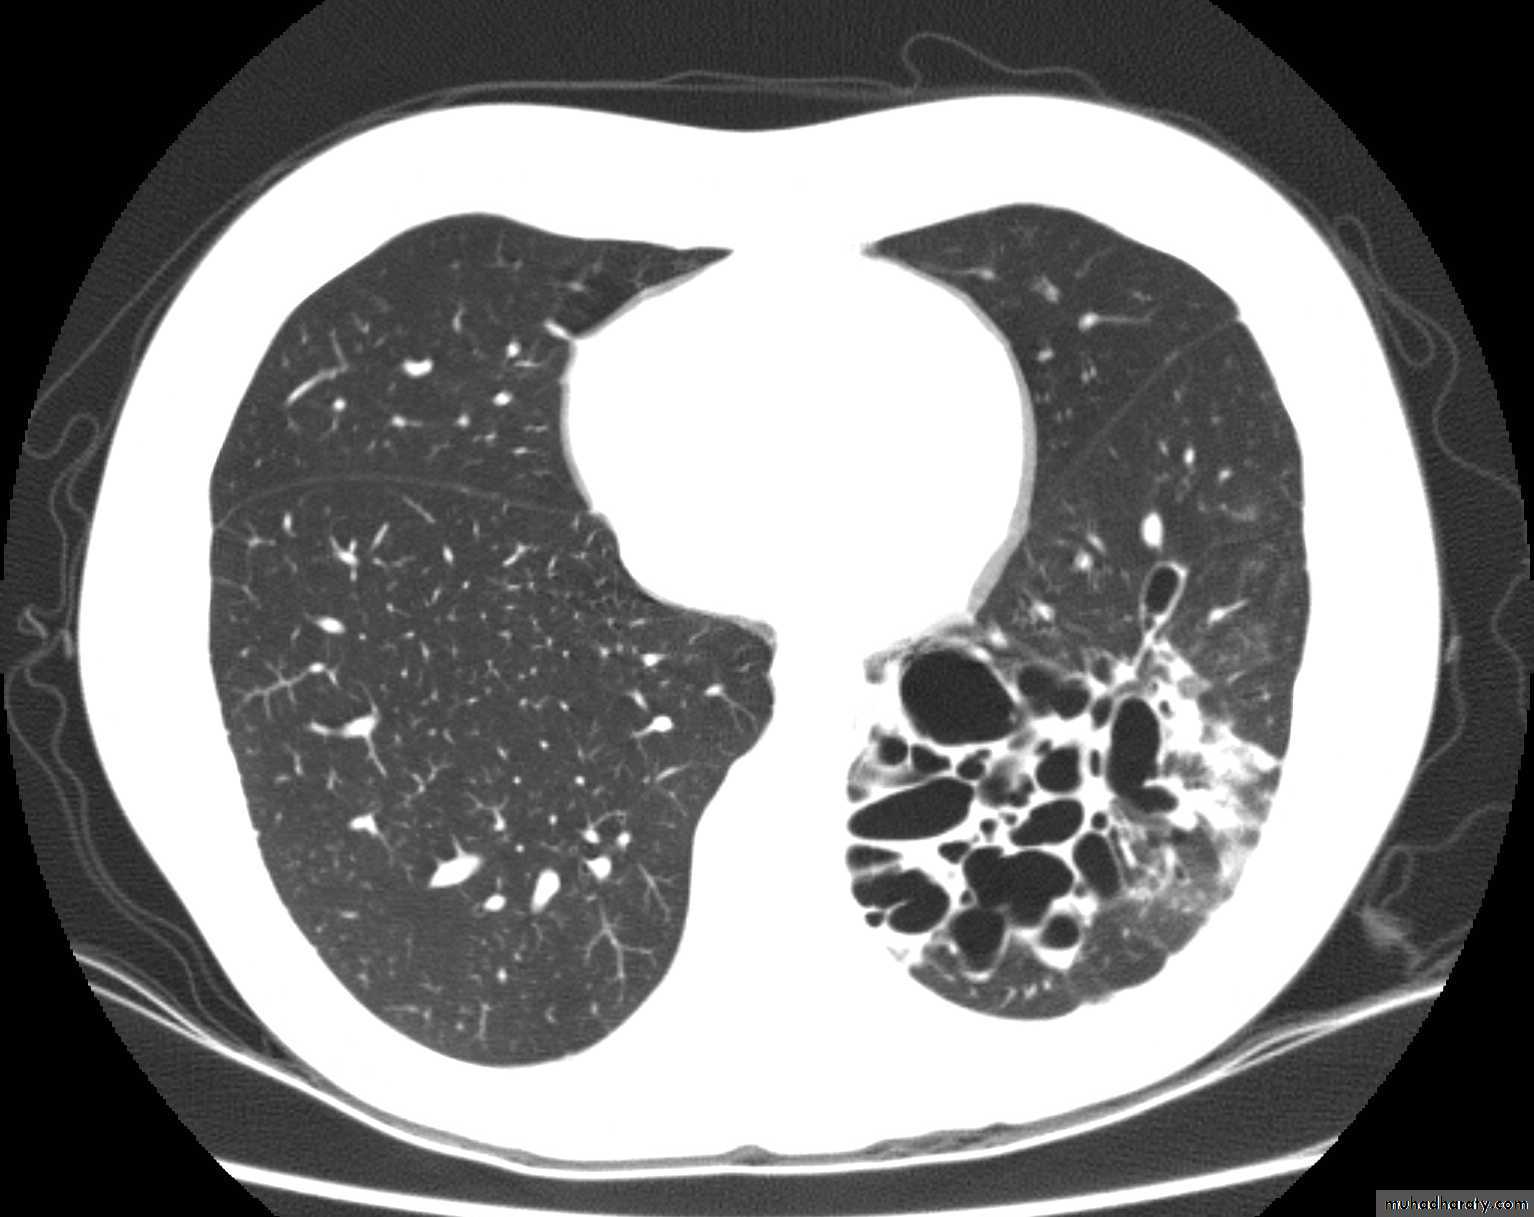

2-CT scan: is the imaging method of choice it shows Bronchial dilatation and wall thickening

• 1-CXR :The plain chest radiograph is abnormal but generally nondiagnostic, the common findings are

• increased lung markings,

• atelectasis,

• air-fluid levels

• Cavities which fill and empty on serial CXR

• Honey-comb pattern: areas of destroyed lung with compensated overinflated adjacent parenchyma